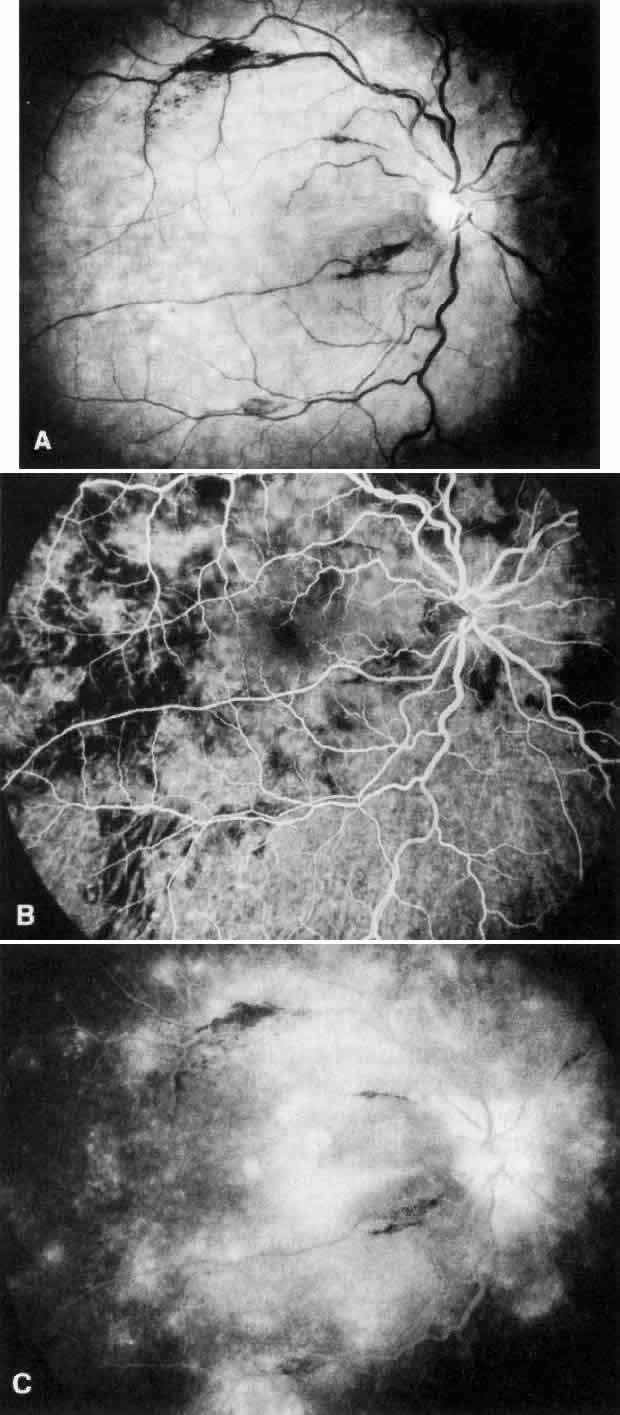

also been described.17 PAPILLORENAL SYNDROME. The papillorenal syndrome has been defined by Bron18 as a dominantly inherited disorder with a bilateral dysplasia of the optic

discs associated with a severe form of glomerulonephritis that may

lead to renal failure. The disc anomaly ranges from morning glory anomaly

or the Handmann anomaly to coloboma or optic pit (Fig. 2). Optic nerve function may be impaired, and in addition there is a risk

of visual loss as a result of serous macular detachment. The pathogenesis

of the renal changes and the genetic mechanism linking the renal

and ocular abnormalities are unknown.  Fig. 2. Papillorenal syndrome with the Handmann optic disc anomaly and macular

changes as a result of chronic macular detachment in a renal transplant

patient. An optic pit and severe hypertensive changes were observed

in his brother, who also received a renal transplant (see Fig. 1). Poor renal function had been recorded in six other family members in

three generations. Fig. 2. Papillorenal syndrome with the Handmann optic disc anomaly and macular

changes as a result of chronic macular detachment in a renal transplant

patient. An optic pit and severe hypertensive changes were observed

in his brother, who also received a renal transplant (see Fig. 1). Poor renal function had been recorded in six other family members in

three generations.